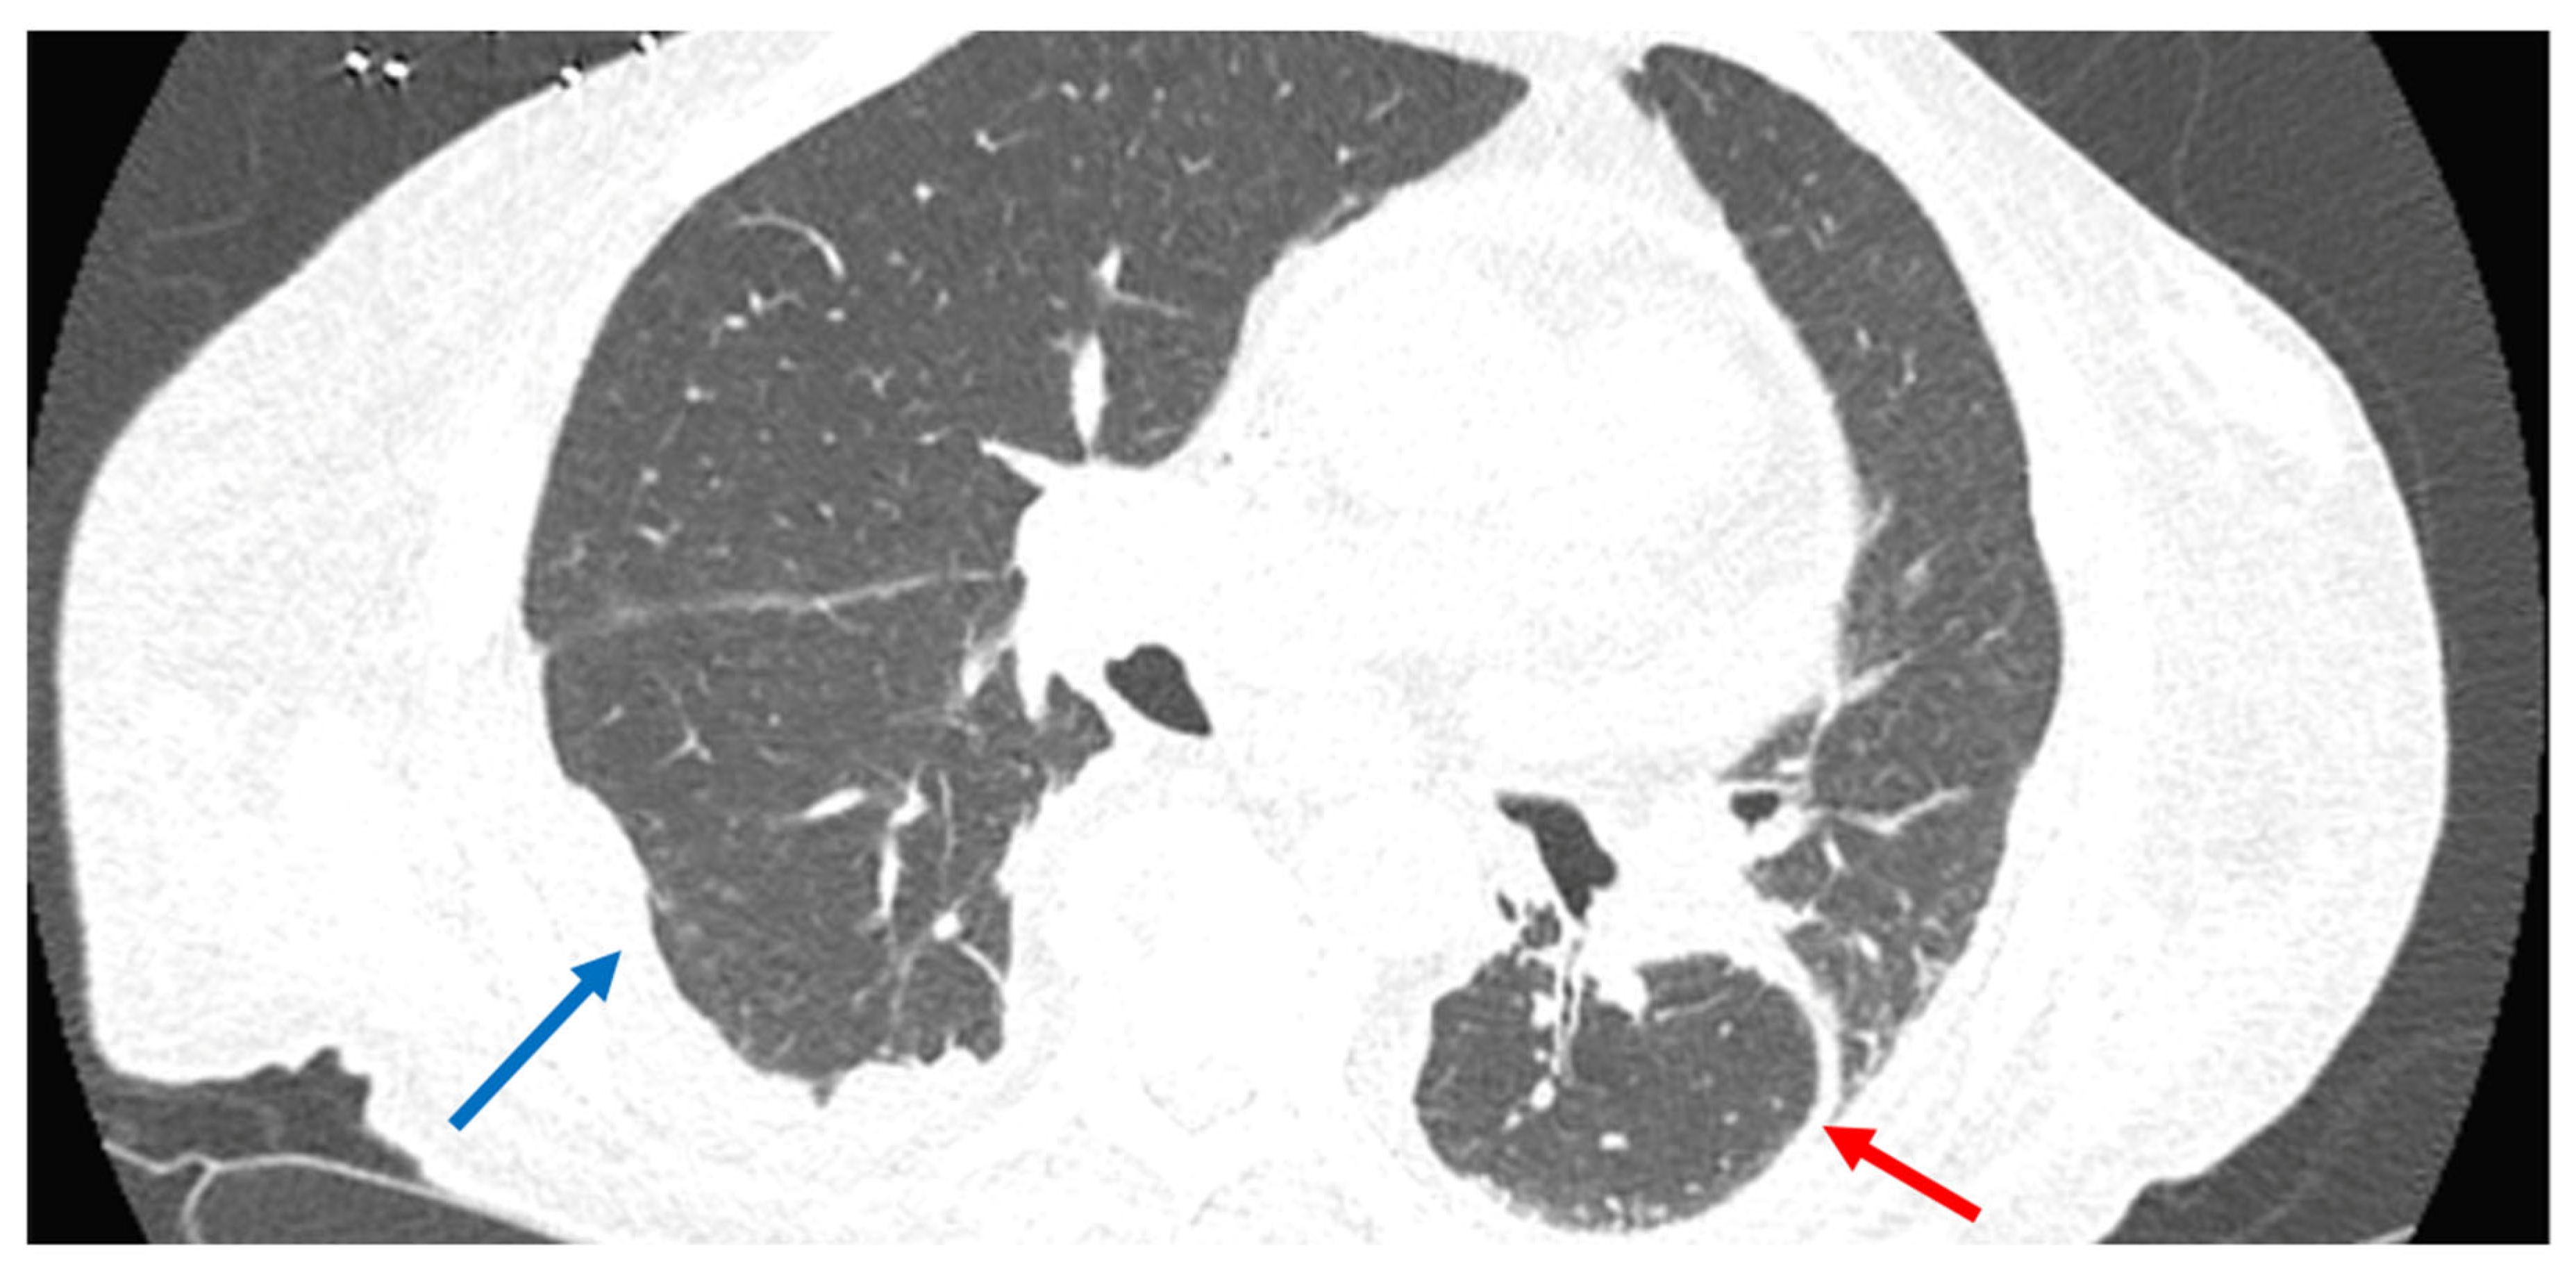

2. Case Presentation